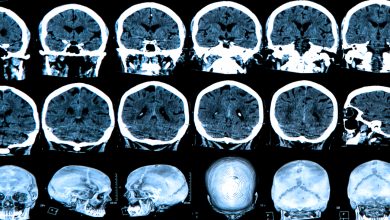

Noticias, avances y análisis sobre investigación clínica, con información verificada sobre estudios, ensayos, regulación y evidencia científica en salud.